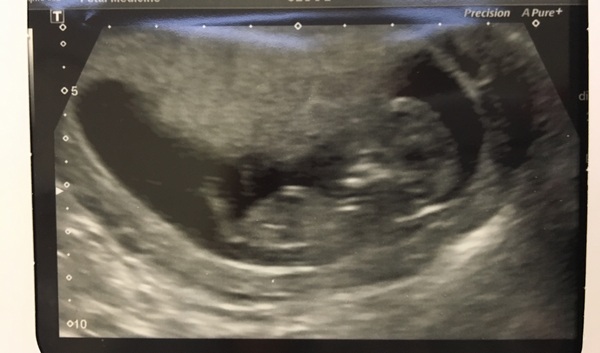

And he or she is!! Any guesses on blue or pink?!

mrspage from that pic I would say blue - but I would rather see 20week scan before I stick with my guess 👍🏼

We have a feeling it's blue as well!!

Ahh mrspage what a lovely scan pic. How exciting! Mine feels so far away.